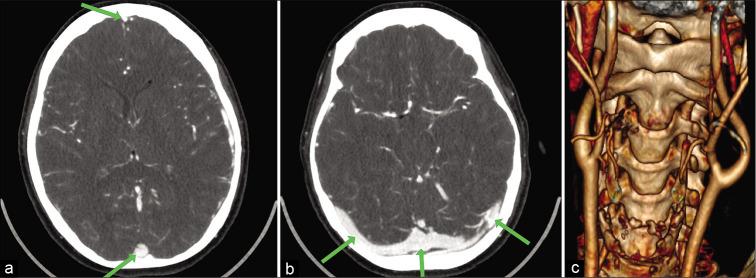

A 38-year-old woman, with no medical history, was admitted in the emergency unit with acute onset of headache, dizziness, and vomiting. On the diagnostic imaging studies (CT venography and MRI) a near total occlusion of all cerebral venous sinuses and a large CBT (Shambin Type II) were diagnosed. Initially, the patient was treated with anticoagulants for the thrombosis and with lumbo-peritoneal (LP) shunt for the management of pseudotumor cerebri. At a second stage, after resolution of the cerebral sinus thrombosis, the CBT was completely resected under electrophysiological monitoring, without preoperative embolization. At 1-year follow-up, the patient is neurologically intact with functioning LP shunt, patent cerebral venous sinuses, without tumor recurrence.

一名38岁无病史女性因突发头痛、头晕和呕吐入住急诊科。经诊断性影像学检查(CT静脉造影和MRI),诊断为所有脑静脉窦几乎完全闭塞以及一个大型CBT(Shambin II型)。最初,患者接受抗凝治疗以处理血栓形成,并采用腰大池-腹腔(LP)分流术治疗假性脑瘤。在第二阶段,脑静脉窦血栓溶解后,在电生理监测下完全切除CBT,未进行术前栓塞。随访1年,患者神经功能完好,LP分流管功能正常,脑静脉窦通畅,无肿瘤复发。